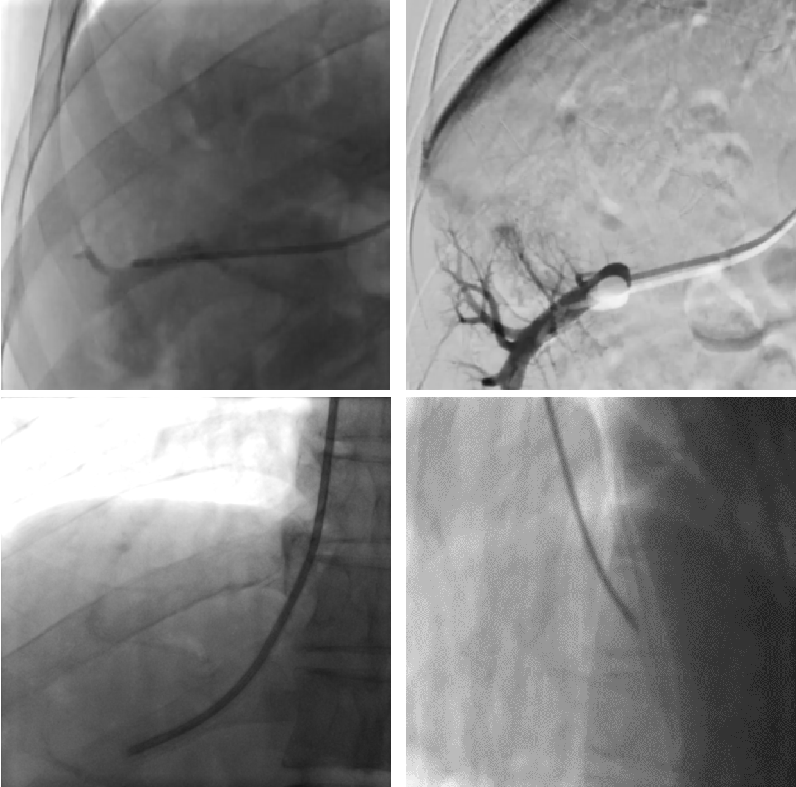

沿颈内静脉-上腔静脉-右心房-下腔静脉-肝静脉穿刺入肝

经肝胆介入团队病情讨论,最终决定为张先生实施经颈内静脉肝穿活检术。在肝胆介入科张跃伟主任指导下,廖勇、刘影及任志忠医师于DSA 透视下首先从右侧颈内静脉建立静脉通路,将导管经颈内静脉、上腔静脉、右心房、下腔静脉进入目标肝静脉。

通过造影剂确认了肝静脉通畅及明确肝静脉走行、与下腔静脉角度等之后,医生们将活检针顺着导引器插入肝脏,顺利穿刺取出了2~3块肝组织样本送检。检查进一步明确了患者门脉高压的诊断,为其开展后续治疗打下了良好的基础。